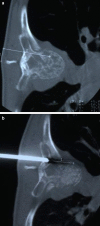

Biopsies of lesions in the spine are often challenging procedures with significant risk of complications. CT-guided needle biopsies could lower these risks but uncertainties still exist about the diagnostic accuracy. Aim of this retrospective study was to evaluate the diagnostic accuracy of CT-guided needle biopsies for bone lesions of the spine. We retrieved the results of 430 core needle biopsies carried out over the past fifteen years at the authors' institute and examined the results obtained. Of the 430 biopsies performed, in 401 cases the right diagnosis was made with the first CT-guided needle biopsy (93.3% accuracy rate). Highest accuracy rates were obtained in primary and secondary malignant lesions. Most false negative results were found in cervical lesions and in benign, pseudotumoral, inflammatory, and systemic pathologies. There were only 9 complications (5 transient paresis, 4 haematomas that resolved spontaneously) that had no influence on the treatment strategy, nor on the patient's outcome. In conclusion we can assert that this technique is reliable and safe and should be considered the gold standard in biopsies of the spine.